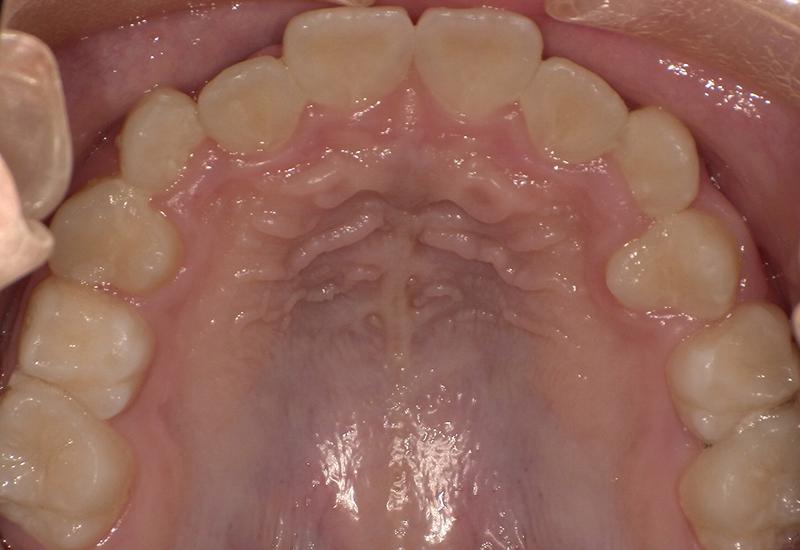

症例① シェイプメモリーアライナーによる下顎の前歯の矯正

治療期間 7ヶ月

治療時の年齢/性別 68歳 / 女性

かかった治療費 440,000円

治療方法 シェイプメモリーアライナー

注意点・詳細

• 根管治療をしてある歯はなるべく動かさない

• 下の前歯の歯の形を少しだけ小さく整えた